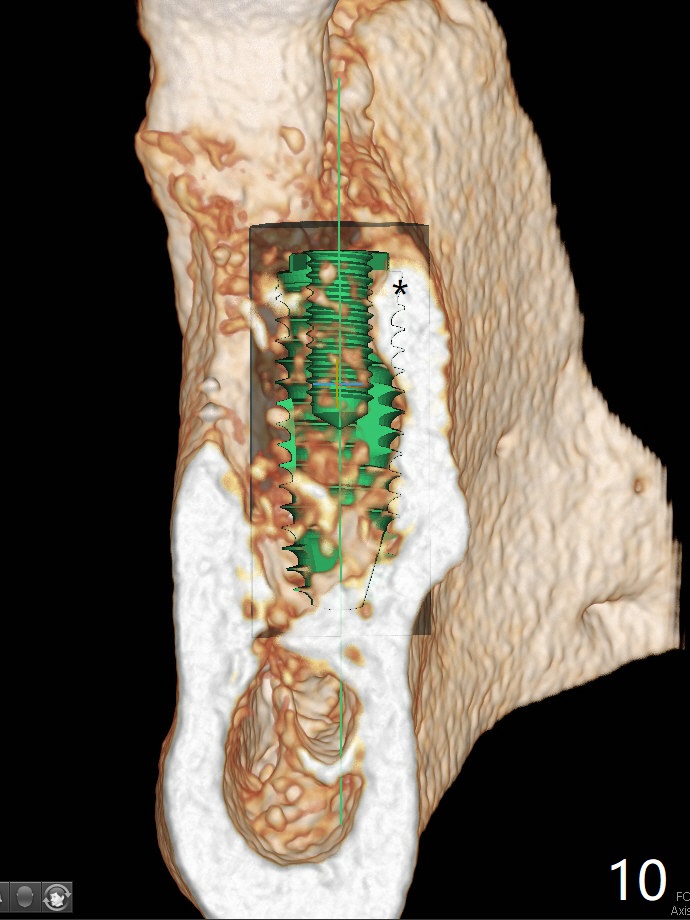

Extraction of the tooth #19 with large PARL (Fig.1,2) confirms the loss of buccal plate, but the crestal bone exists. After failure to place an implant in the middle socket with removal of the lingual septal bone, socket preservation is done with PRF and sticky bone (Fig.3). There is possibility to place a ~4 mm implant in the mesial socket (Fig.4). Or just drop a 5x11 mm Bicon Implant into the large socket, surrounded by sticky bone. When periodontal dressing is removed 18 days postop, the bone graft seems to remain to be "sticky" yellowish, while the granulation tissue has started to grow into the center of the socket from the previously buccal and lingual furcae (Fig.5 reddish). Granulation tissue seems to cover the bone graft (Fig.6), although there is smells when the periodontal dressing is removed. Bone height reduces nearly 3 months postop (Fig.7). The buccal plate collapses (Fig.8), but there seems no further bone loss 4 months postop (Fig.9). Because of buccal plate loss, an implant will be placed lingually with guide (Fig.10-12 green). Bone graft may be placed buccally after implant placement with probing.